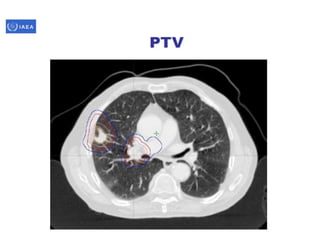

Volume definition

• Prerequisite for 3-D treatment planning.

• ICRU reports50 & 62 define & describe target

& critical structure volumes.

• volumes defined prior to treatment planning

– Gross tumor volume (GTV).

– Clinical target volume (CTV).

• Defined during the treatment planning process

– Planning target volume (PTV).

– Organs at risk.

• As a result of treatment planning, volumes described.

– Treated volume (TV).

– Irradiated volume (IRV).